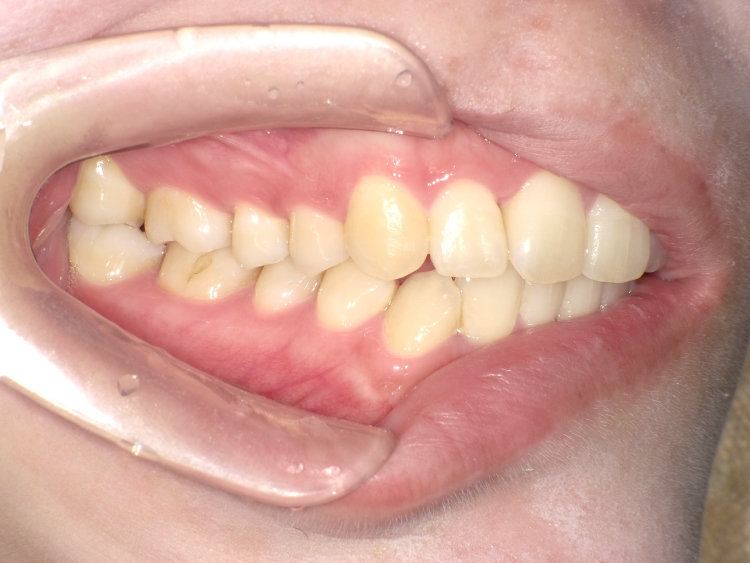

症例6

治療前

治療後

| 主訴 | 右上2番前にでてるのが気になる 上のみ部分矯正希望 |

|---|---|

| 治療 期間 |

約4ヶ月 |

| 治療費 | 247,500円(税込)/調整費用別途 |

| 治療 内容 |

上の前歯部にワイヤーを着けて進めていく、プチ矯正で施術。 |

| 治療の リスク |

奥歯を動かさないので前に出して並べていく。 歯を動かすことで、歯茎が下がるリスクある。 装置による清掃の難しさから、歯肉炎や歯周病、虫歯のリスクが高まる。 矯正終了後は、リテーナーを使用し、後戻りを防ぐ必要がある。 |